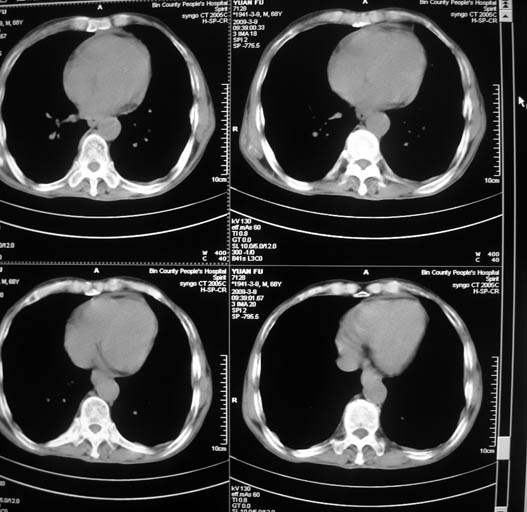

标题: CT18577:男,68岁,左肺占位。 [打印本页]

标题: CT18577:男,68岁,左肺占位。

男,68岁,左上肺占位,肺门淋巴结转移?

1)考虑左肺上叶尖段周围型肺癌并阻塞性肺炎,纵隔淋巴结转移。2)心包少量积液。

1)考虑左肺上叶尖段周围型肺癌并阻塞性肺炎,纵隔淋巴结转移。2)心包少量积液

1)考虑左肺上叶尖段周围型肺癌并阻塞性肺炎,纵隔淋巴结转移。

2)心包少量积液。